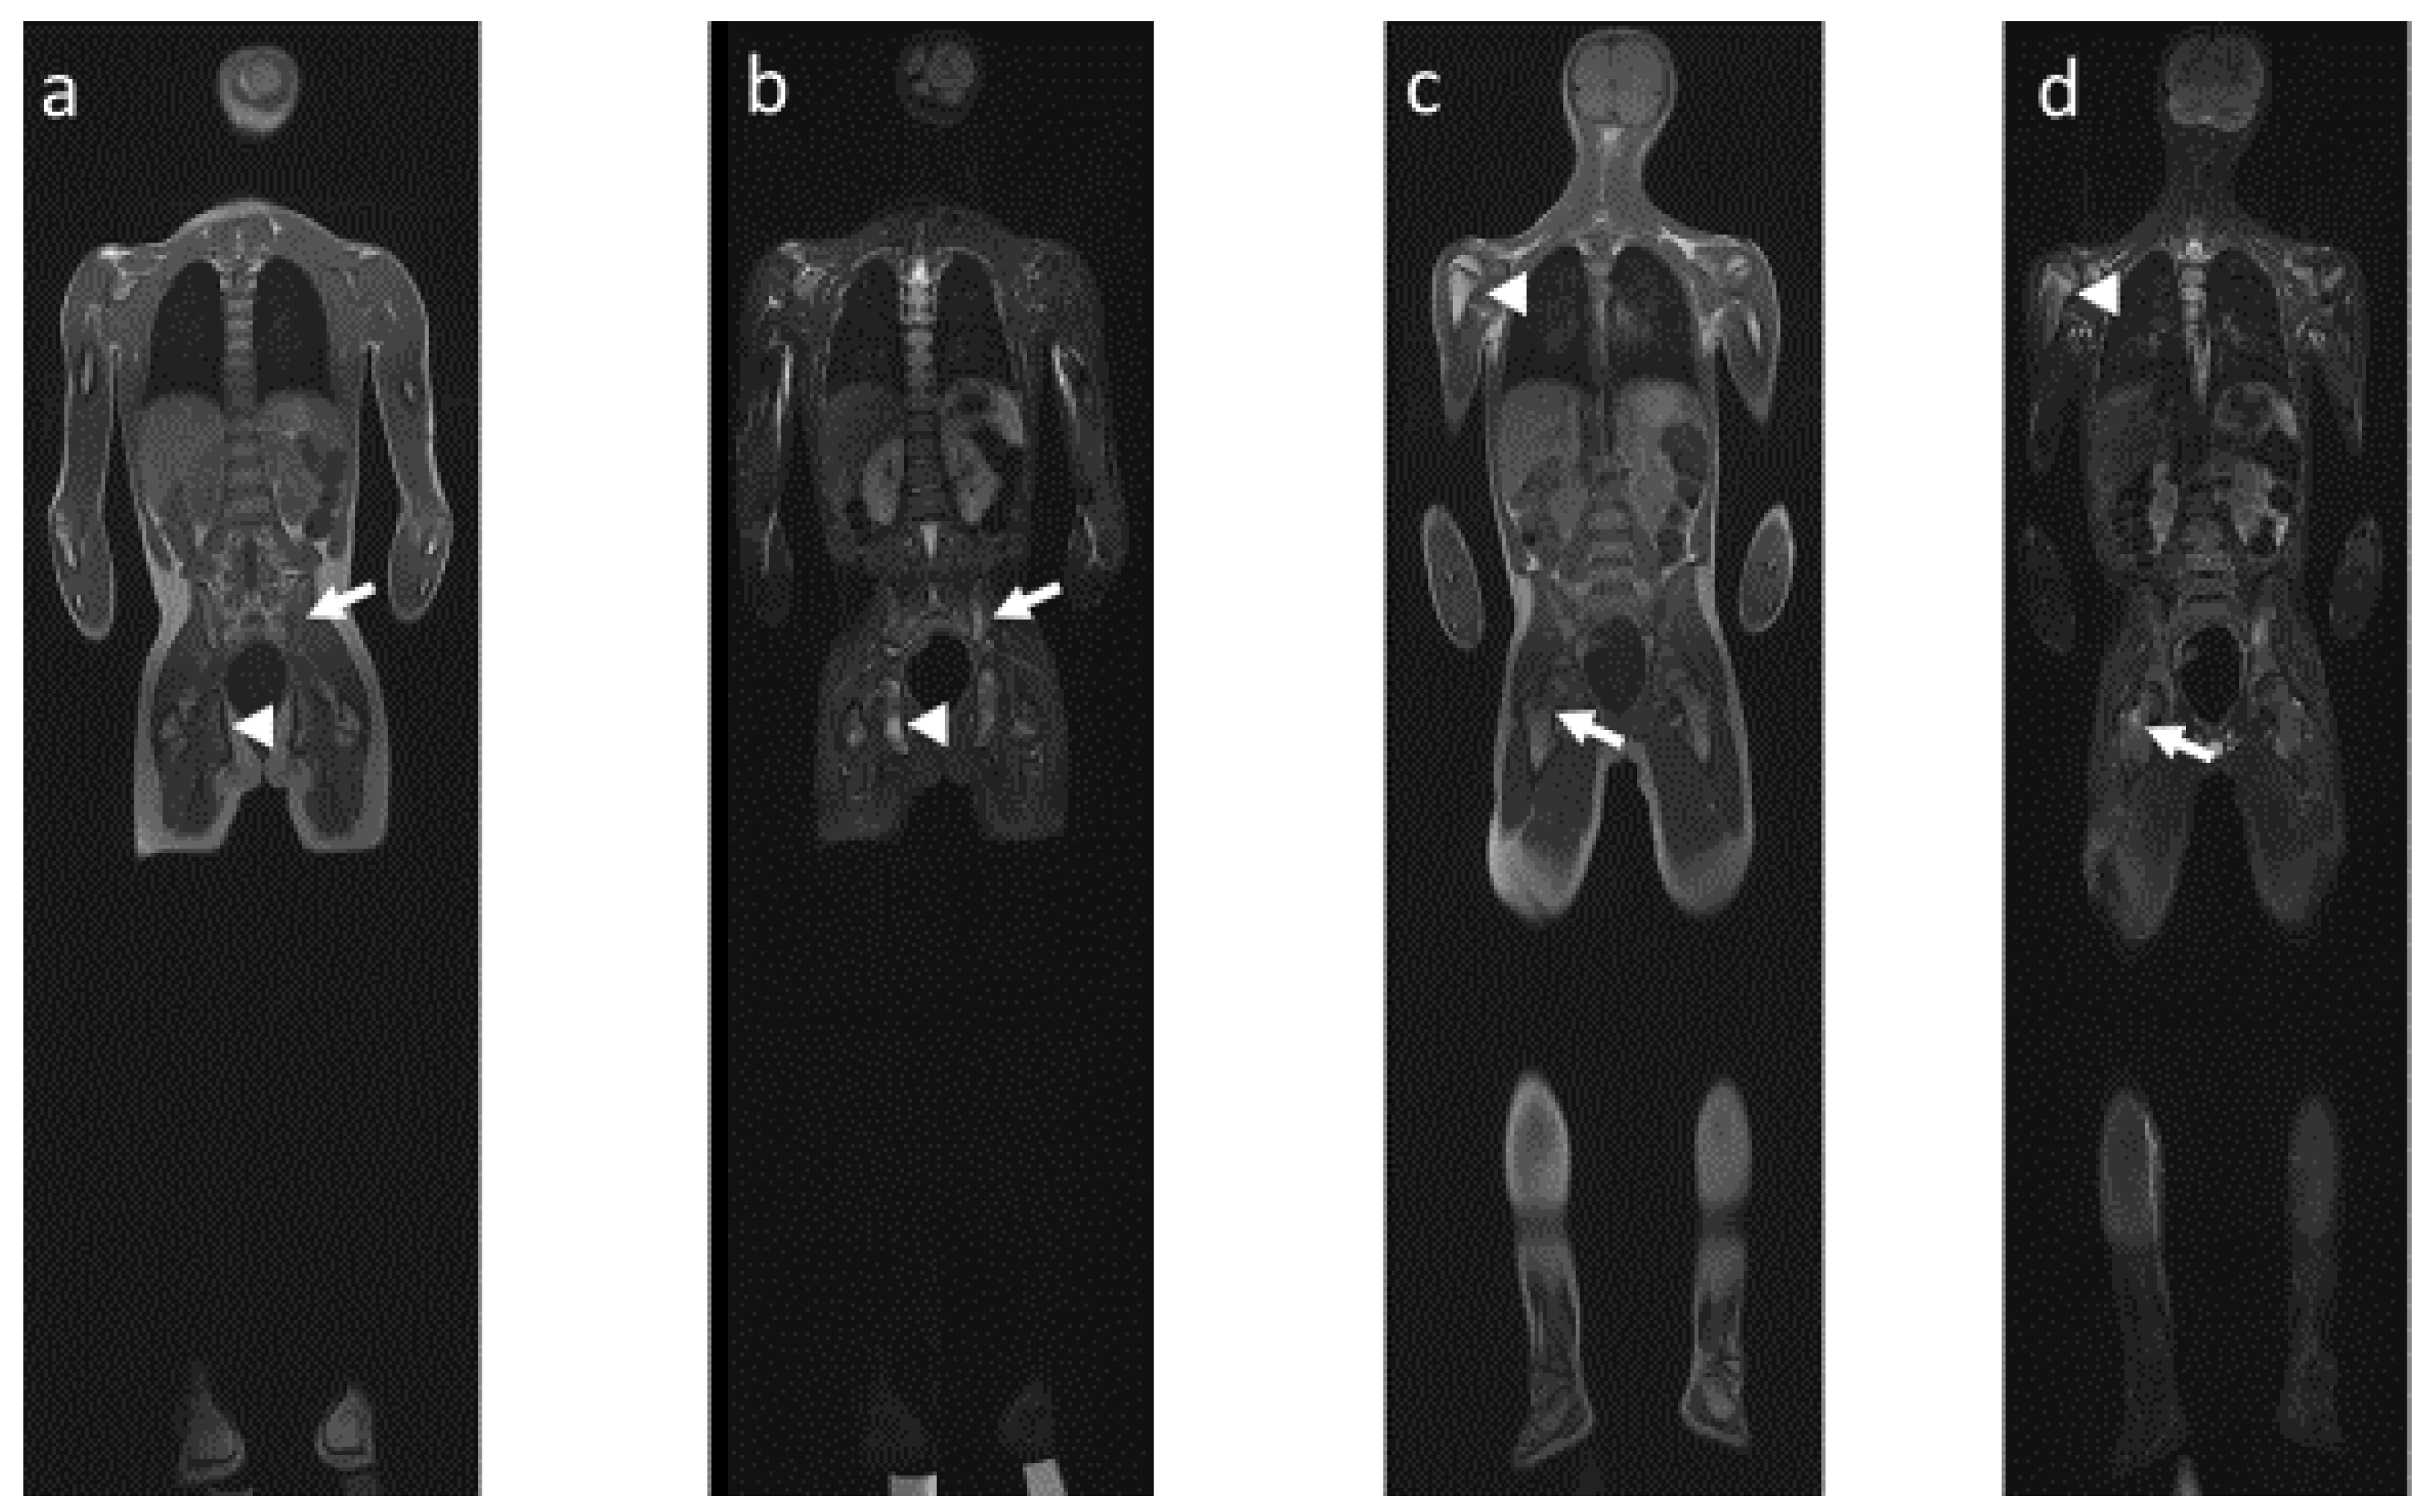

4.2. Radiological Particularities of Each Entity

- (1)

- Bone lesions

- (2)

- Vertebral and paravertebral involvement

- (3)

- Sacroiliac involvement